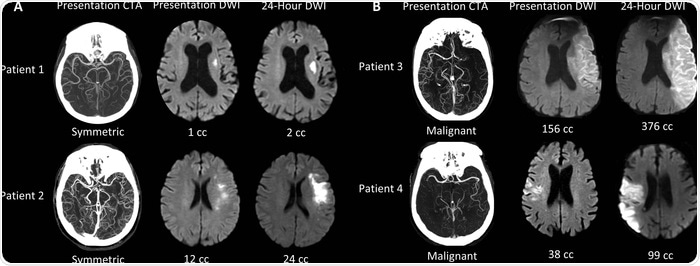

It turns out that the growth of the ischemic core varies widely amongst patients. Our research, confirmed by work at other centers, shows that nearly half of all patients have a slow growth pattern and may be treated 24 hours after stroke onset, and perhaps even later.

What link did you find between ischemic core growth and blood flow in collateral blood vessels?

The great variation in the growth of the ischemic core in patients with LVO is due to differences in the collateral circulation. The collateral circulation are arteries that provide blood to parts of the brain that are endangered.

The collaterals come from other large arteries that are not occluded. The variation in collateral blood flow is extraordinarily large, and because of that, the growth of ischemic cores is also very different from patient to patient.

We are creating a machine learning algorithm that can identify LVO patients with symmetric collateral circulation that is a marker of small cores that are growing slowly. This is one of several algorithms that we are combining into a suite of algorithms that are capable of capturing all of the key information for the evaluation of the acute stroke patient.